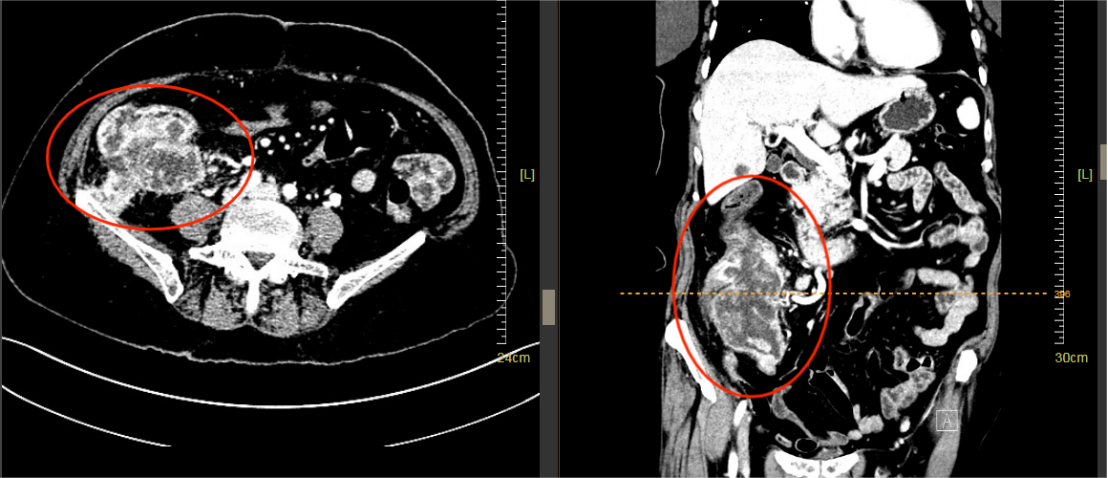

时间回溯到半年前,王先生因持续腹胀、排便异常等症状来到和祐医院消化内科就诊。通过胃肠镜等一系列检查后,王先生被诊断为局部晚期直肠癌。随后在放疗科和肿瘤内科开展为期半年的新辅助治疗。